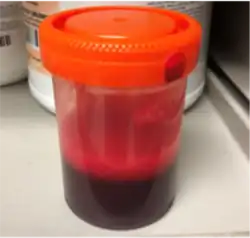

Thoracentesis

Although imaging techniques can demonstrate that fluid is present within the pleural space, it may be unclear what this fluid represents. To establish the nature of the fluid, a sample can be removed by inserting a needle into the pleural cavity in a procedure known as a thoracentesis or pleural tap. In this context, the most important assessment of the pleural fluid is the percentage by volume that is taken up by red blood cells (the hematocrit) A hemothorax is defined as having a hematocrit of at least 50%[6] of that found in the affected person's blood, although the hematocrit of a chronic hemothorax may be between 25 and 50% if additional fluid has been secreted by the pleura.[8] Pleural fluid can dilute hemothoraces in as low as 3–4 days.[5] The red blood cells in the effusion spontaneously break down.[11] Distinguishing the pleural fluid from blood by colour is impossible when the hematocrit value is over 5%.[3] For these reasons, even if there is a hematocrit value under 50%, further investigations can be done in order to figure out if there is a source of bleeding.[5] Hematocrit can be roughly calculated by dividing the red blood cell count of the pleural fluid by 100,000.[6] Thoracentesis is the test most commonly used to diagnose a hemothorax in animals.[28] Hemothorax can itself be a rare complication of thoracentesis if the intercostal artery is punctured.[29]